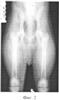

Фиг.3 – рентгенограмма тазобедренного сустава собаки через 30 суток после оперативного вмешательства;

По результатам рентгенологического исследования в послеоперационном периоде установлено, что через 30 суток у животного в правом тазобедренном суставе сформировалась картина, характеризующаяся вывихом бедра, уплощением вертлужной впадины. Замыкательная пластина вертлужной впадины слита с латеральной поверхностью таза, головка бедра уплощена с нарушением архитектоники костных балок, в зоне линии Моргана – значительные экзостозы, шеечно-диафизарный угол – 136° (фиг.3).

В клиническом плане у животного отмечалась атрофия параартикулярных мышц на стороне повреждения, слабость опоры тазовых конечностей, вихляющая походка, хромота опорного типа, внутренняя ротация больного бедра, ограничение отведения бедра в сторону до 20°. Наряду с этим были выражены симптомы «щелчка» и «насоса» в суставе, относительное укорочение правой тазовой конечности на 1,4 см, а также положительные симптомы Ortolani и Bardens.